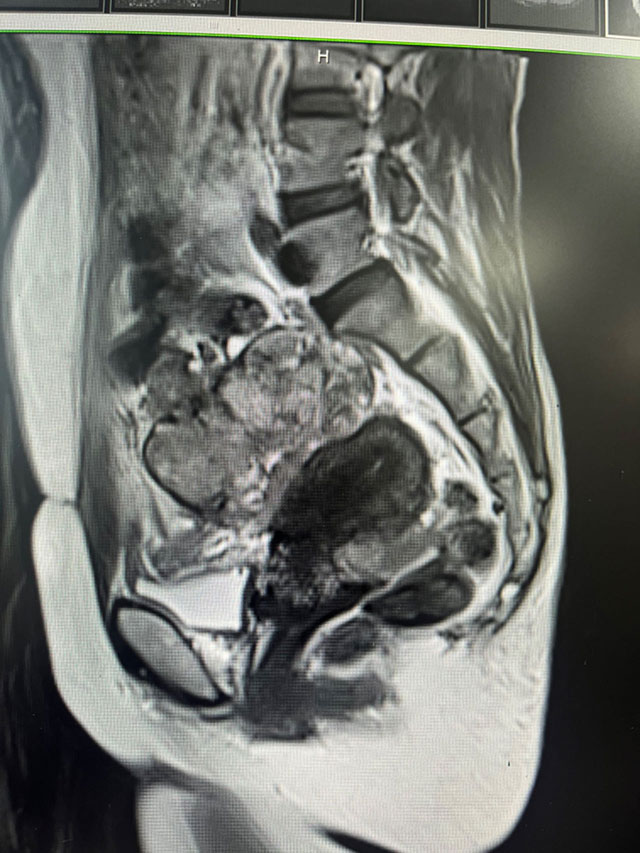

320多斤女生,切胃……

29岁的小梅(化名)早已忘了“轻盈”是什么感觉——身高172cm的她,体重飙过320斤,换算成体重指数(BMI)更是达到54kg/m²,远超“超级肥胖”(BMI>50)的诊断标准,妥妥的“极重度肥胖”。肥胖带来多病缠身  肥胖带来的...